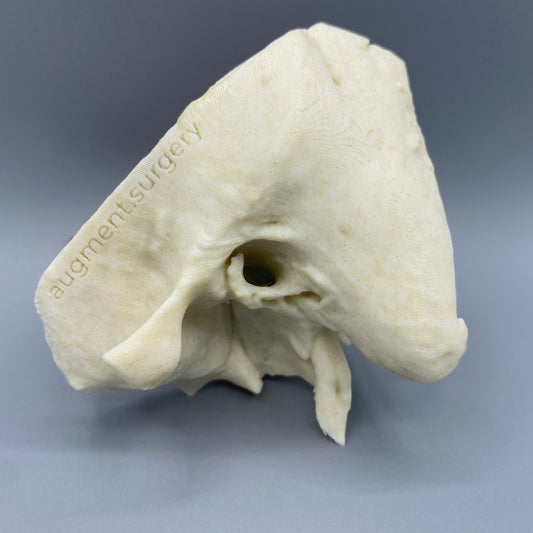

Plant-based surgical simulators made in the U.S.A.

Dissect each one to learn human temporal bone anatomy, hearing and vestibular systems.

Customize anatomy, colors, quantities, and more by contacting michelle@augment.surgery